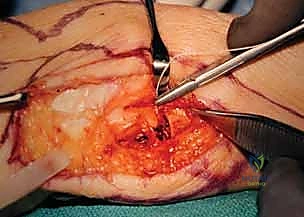

Deep Dissection and Extraperiosteal Exposure

With the nerve protected, we proceed to the deep fascial layer. We incise the deep fascia longitudinally, precisely developing the interval between the Extensor Carpi Ulnaris (ECU) tendon dorsally and the Flexor Carpi Ulnaris (FCU) tendon volarly. Using blunt retractors, we retract the ECU dorsally and the FCU volarly, revealing the distal ulnar diaphysis and the metaphyseal flare.

Our approach to the bone is strictly extraperiosteal. We incise the periosteum longitudinally along the ulnar shaft and carefully elevate it using a sharp periosteal elevator. It is imperative to preserve the periosteal sleeve as much as possible, as we will later close it over the pseudoarthrosis gap to act as a barrier against hematoma and bone regeneration. As we dissect volarly around the ulnar neck, we encounter the Pronator Quadratus (PQ) muscle. We meticulously elevate the ulnar insertion of the PQ, preserving its muscle belly, as this will serve as our primary interpositional soft tissue flap.

Clinical & Radiographic Imaging Archive